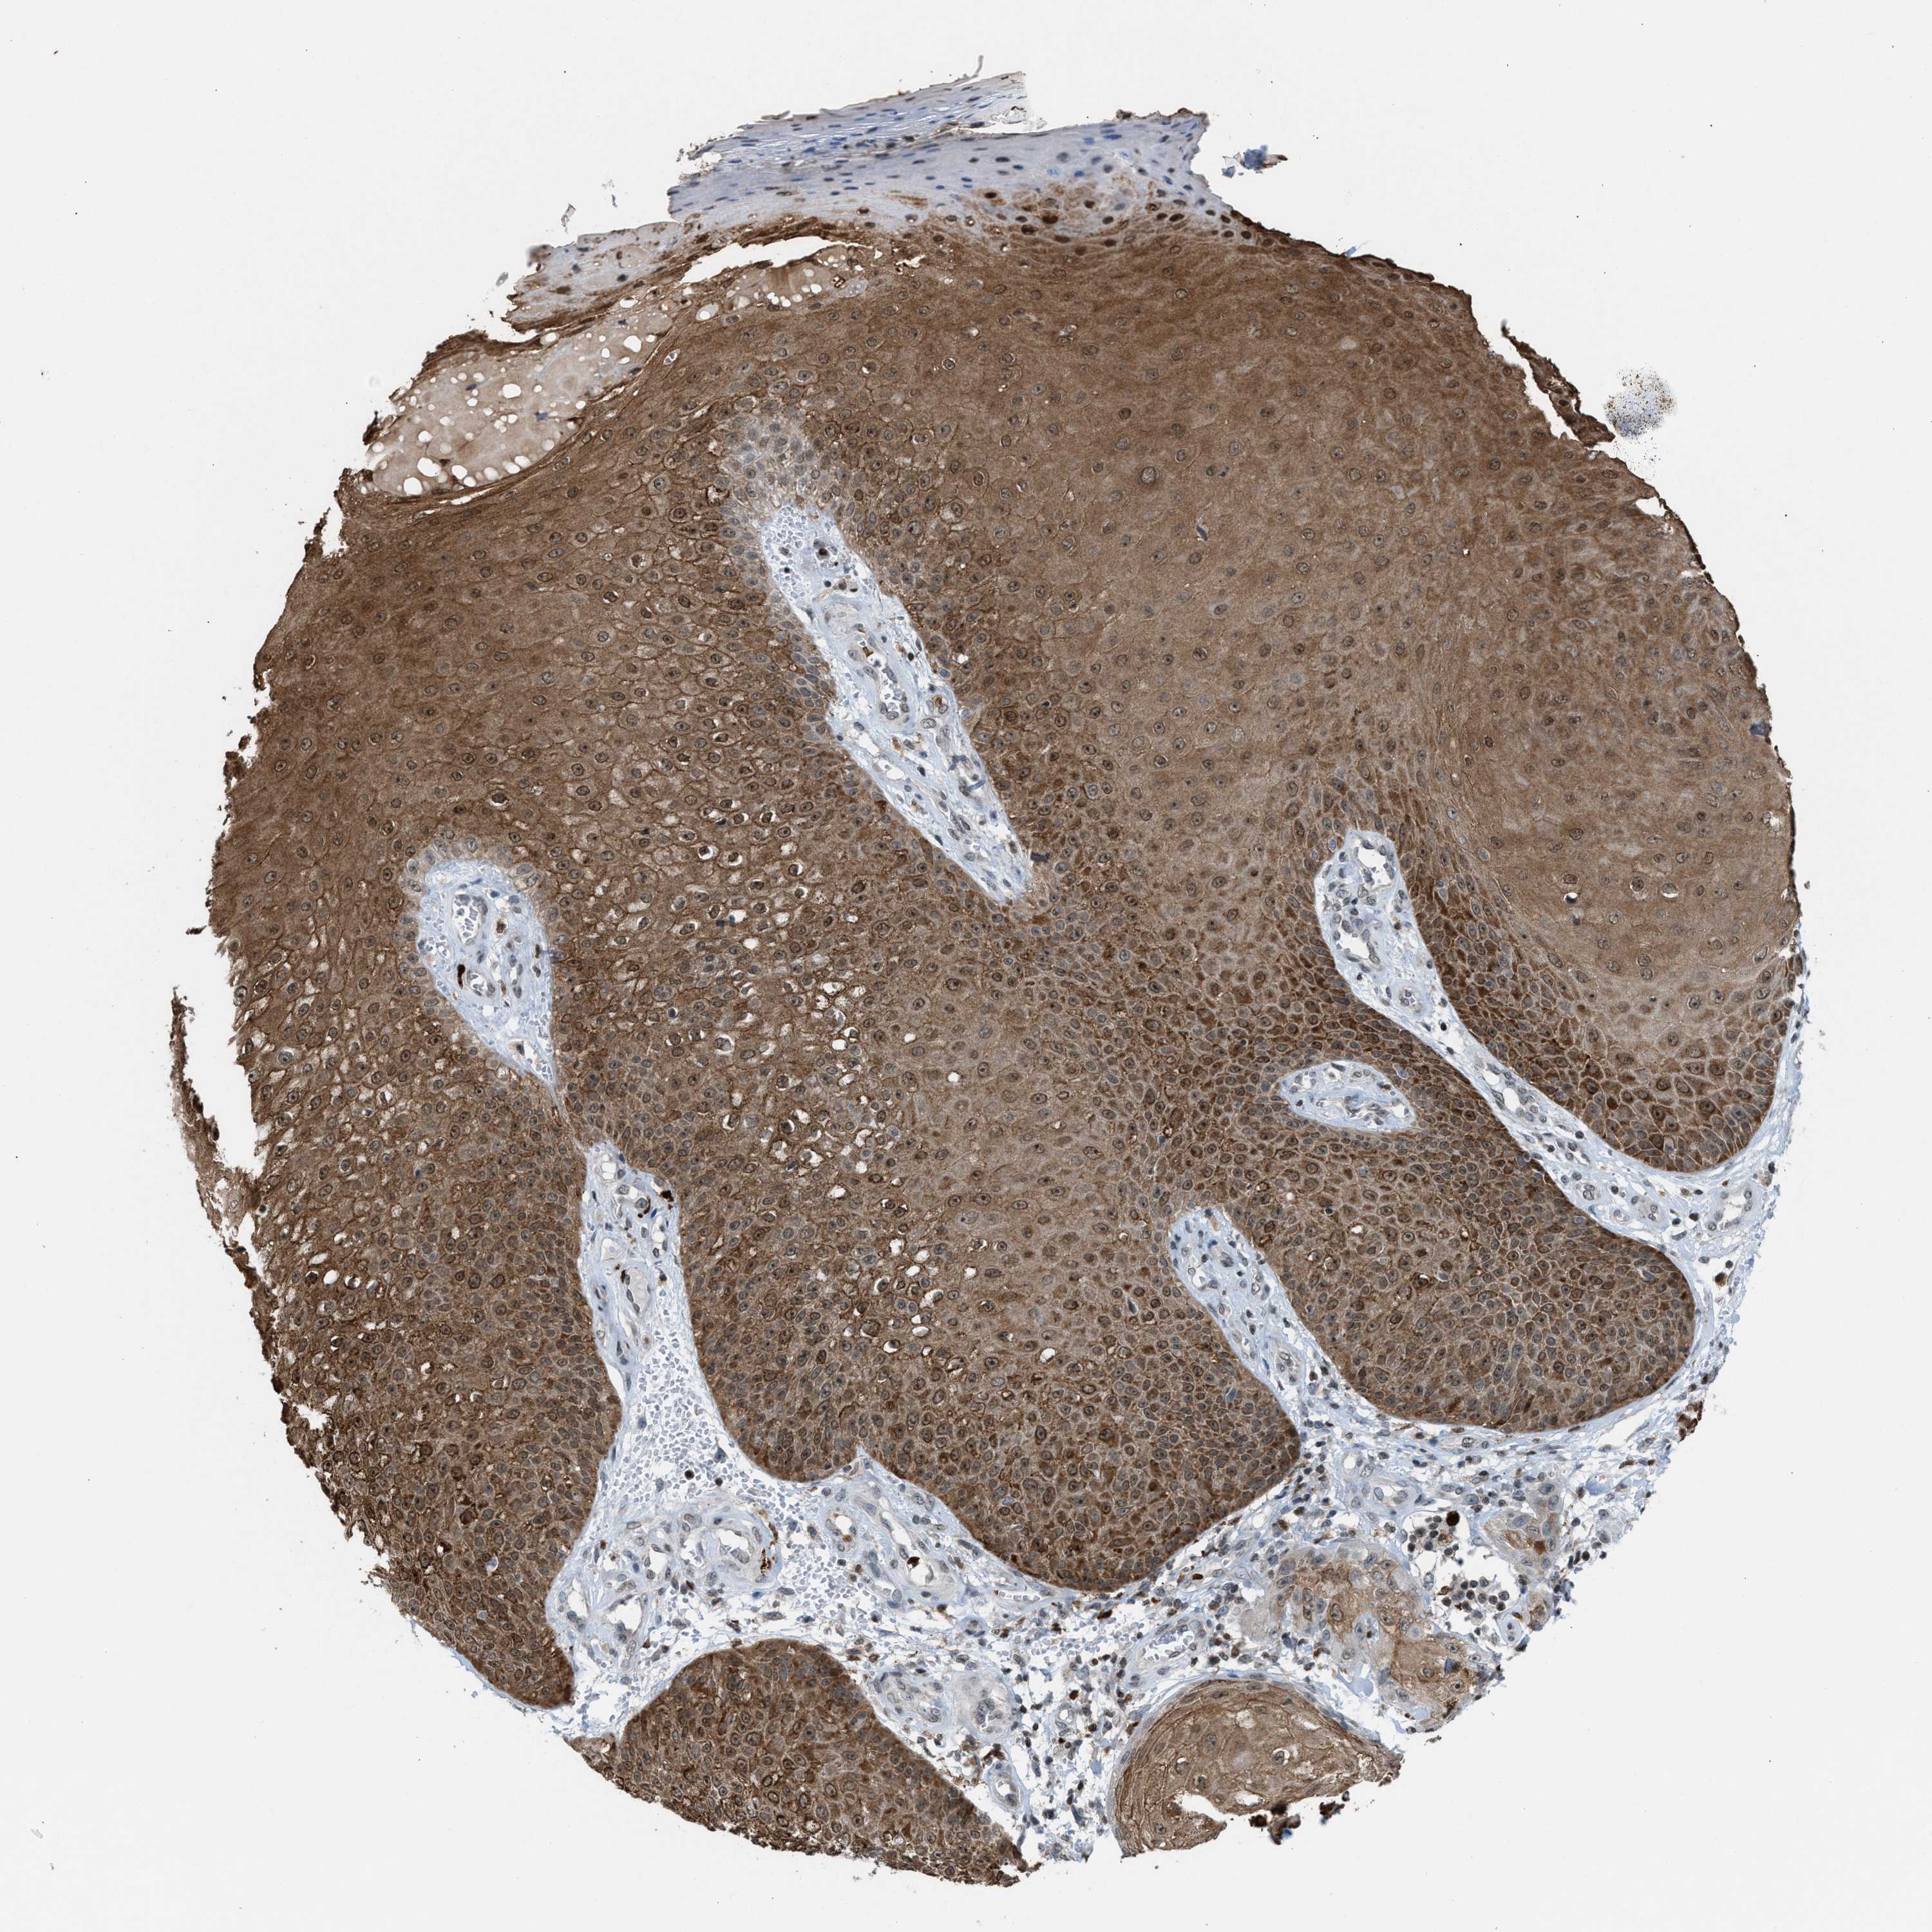

SKIN CANCER - Protein expressioni

A mouse-over function shows sample information and annotation data. Click on an image to view it in a full screen mode. Samples can be filtered based on level of antibody staining by selecting one or several of the following categories: high, medium, low and not detected. The assay and annotation is described here.

Each image is clickable and will lead to virtual microscopy that enables deeper exploration of all samples and also displays staining intensity scores, fraction scores and subcellular localization as well as patient and tissue information for each sample.

Antibody HPA022470

Staining

High

Intensity

Strong

Quantity

>75%

Location

Nuclear

Squamous cell carcinoma, NOS